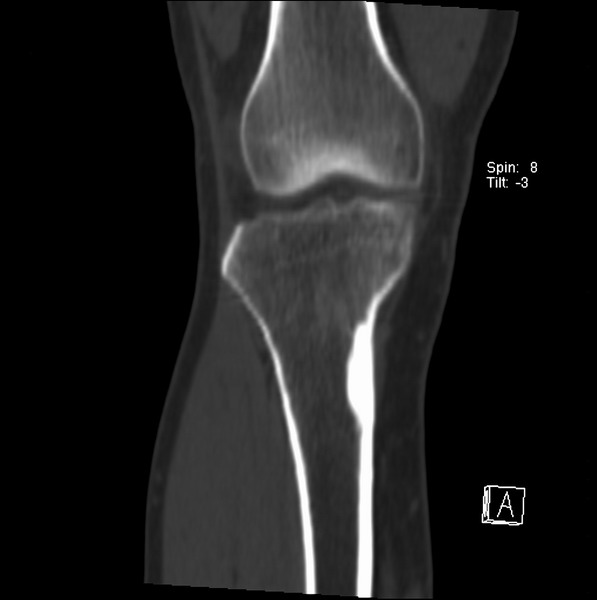

右侧膝关节疼痛一月

男、48

股骨下段、胫骨上段。

1、股骨干骺端病变考虑干骺端纤维性皮质缺损愈后(非骨化性纤维瘤)改变,胫骨近端内生骨瘤(或干骺端纤维性皮质缺损愈后改变);

2、骨关节炎,骨质增生,股骨外侧髁退变性囊肿(关节面软骨下囊肿);

1、股骨干骺端病变考虑干骺端纤维性皮质缺损愈后(非骨化性纤维瘤)改变,胫骨近端内生骨瘤;

股骨干骺端病变考虑非骨化性纤维瘤。